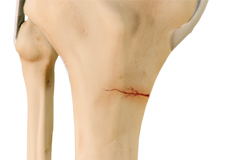

Articular Cartilage Injury

Articular or hyaline cartilage is the tissue lining the surface of the two bones in the knee joint. Cartilage helps the bones move smoothly against each other and can withstand the weight of the body during activities such as running and jumping.

Chondral or Articular Cartilage Defects

The articular or hyaline cartilage is the tissue lining the surface of the two bones in the knee joint. Cartilage helps the bones move smoothly against each other and can withstand the weight of your body during activities such as running and jumping.

Osteochondral Defect of the Knee

An osteochondral defect, also commonly known as osteochondritis dissecans, of the knee refers to a damage or injury to the smooth articular cartilage surrounding the knee joint and the bone underneath the cartilage. The degree of damage may range from a rupture of the cartilage to a slight crack of the bone to a piece of the bone breaking off within the joint.